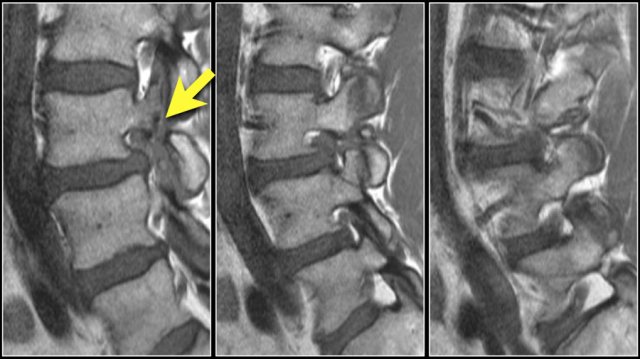

The findings at the different levels 1-4 are:

1. At the level of the disc there is minimal spinal canal narrowing by bulging of the disc and facet arthrosis.

2. At this level there is severe spinal canal stenosis due to bulging disc and facet arthrosis.

There is also an annular tear (high signal) through which the disc herniates (yellow arrow)

3. At the level of the lateral recess, there is a focal herniation of disc material compressing the L5 nerve (yellow arrow).

This is called an extrusion, because the distance between the edges of the disc material is greater than the distance at the base.

4. Compressed L5 nerve (blue arrow) within the lateral recess.

The herniated disc has migrated caudally and is seen as an oval structure anterior to the nerve.

The herniated disc is uncontained, i.e. not covered by fibers of the annulus.